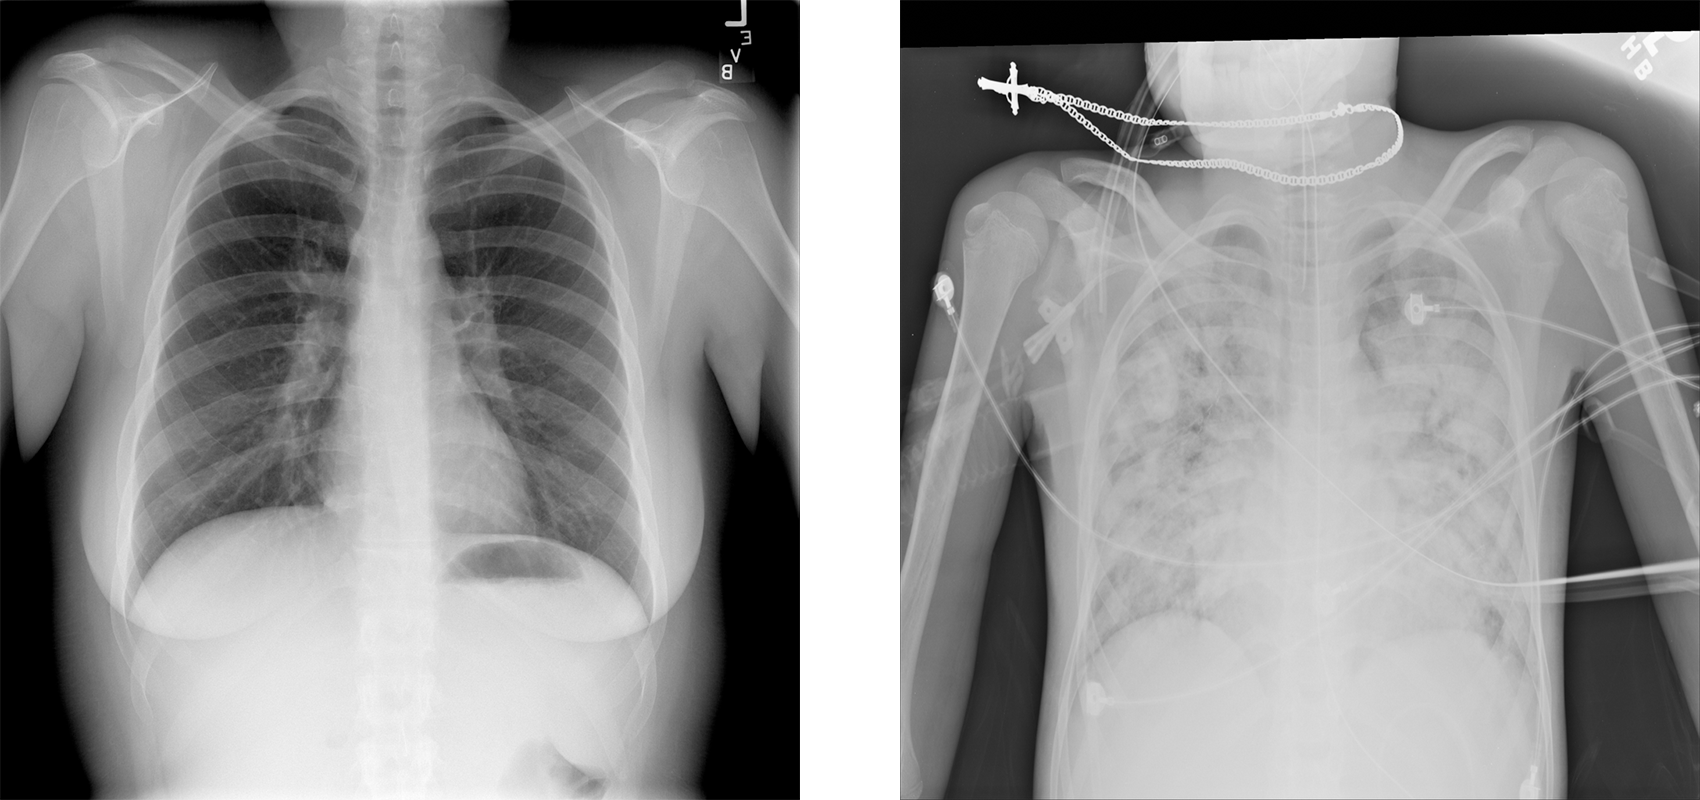

NoisyCXR: NoisyCXR is a binary classification task aimed at identifying the presence of pneumonia in chest X-ray images. This dataset was developed to emulate the real-world label noise in medical images, instead of adding artificial noise to clean datasets. Specifically, Our implementation details followed the methodologies described in [2]. The X ray images in NoisyCXR are all provided by National Institutes of Health (NIH), with original labels (termed ‘NIH labels’) that are generated using a language-processing approach based on radiological reports. These labels encompass 14 classes representing various abnormalities, with one single X-ray potentially tagged with multiple NIH labels. However, this automated labeling process was proved to introduce certain degree of label noise. The labels were then manually validated and reissued by Radiological Society of North America (termed RSNA labels), which are regarded as clean labels in our study. The RNSA labels include three groups: normal, pneumonia-like opacity, and other abnormalities. For the construction of the NoisyCXR dataset’s clean labels, cases annotated with ’Pneumonia-like opacity’ are classified as ’pneumonia’, and all others are designated as ’no pneumonia’.

We utilized the NIH labels to generate the noisy labels of NoisyCXR. In the case of images labeled as ’Pneumonia’ in the NIH labels, they retain their classification. However, there are many X-ray images with ambiguous terms such as ’consolidation’ or ’infiltration’, which may suggest potential pneumonia but lack definitive confirmation. In order to simulate how label noise really happens in a clinical situation, we attributed all cases with label ’consolidation’ or ’infiltration’ to class ’pneumonia’. For all other labels, encompassing both ’no abnormality’ and any other types of abnormalities, they are categorized under the ’no pneumonia’ class. Through this rigorous process, we have crafted the NoisyCXR dataset, with a noise rate of 40%, thereby providing a robust framework for evaluating the performance of binary classification models in the presence of label noise.

Refer to caption

Figure 5: Sample images in NoisyCXR dataset: no pneumonia / pneumonia